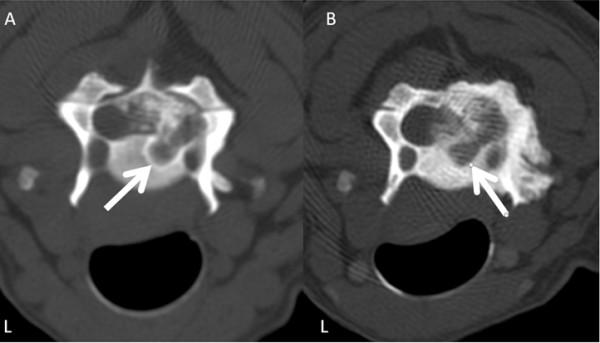

A ten-year-old male standard dachshund was presented with a history of neck pain and progressive gait disturbances. Following a neurological examination and diagnostic imaging, including CT, a neoplastic lesion involving the third and fourth cervical vertebrae was suspected. The lesion included an extradural mass on the right side of the spinal canal causing a local compression of the cervical cord. Surgery, using a modified dorsal laminectomy procedure, was performed in order to decompress the cervical spinal cord. Histopathological examination of the extradural mass indicated that the tumour was a chondroid chordoma. Following discharge, the quality of life for the dog was very good for a sustained period, but clinical signs recurred at 22 months. The dog was euthanased 25 months post-surgery. On post-mortem examination, a regrowth of neoplastic tissue was found to have infiltrated the bone and spinal cord at C3-C4. This is the first report to show that palliative surgery can offer successful long-lasting treatment of chondroid chordoma of the cervical spine in the dog.

一只十岁大的雄性标准贵宾犬,出现颈部疼痛和进行性步态障碍的病史。经过神经学检查和包括 CT 在内的诊断影像学检查后,怀疑第三和第四颈椎有肿瘤病变。病变包括椎管右侧的硬膜外肿块,导致颈脊髓局部受压。为了对颈脊髓进行减压,采用改良的背侧椎板切除术进行了手术。硬膜外肿块的组织病理学检查表明肿瘤为软骨脊索瘤。出院后,狗狗的生活质量在很长一段时间内都非常好,但在 22 个月时临床症状再次出现。手术后 25 个月,狗狗被实施了安乐死。尸检时发现,C3-C4 处的骨和脊髓有肿瘤组织再生并浸润。这是首例报道显示姑息性手术可以为犬颈椎软骨脊索瘤提供成功的长期治疗。